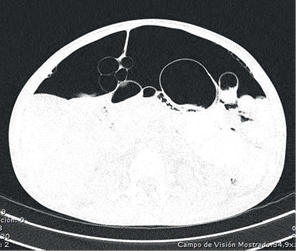

Al no encontrarse signos de irritación peritoneal, se practicó una tomografía toraco-abdominal en la que se observó: derrame pleural bilateral con engrosamiento de las cisuras, bronquiectasias basales bilaterales, atelectasia parcial de ambos lóbulos inferiores, notoria distensión del esófago con sonda en su interior, hidroneumoperitoneo, abundante líquido libre en la cavidad abdominal y distensión de las asas intestinales (figuras 1,2,3).

La distensión abdominal mejoró parcialmente con la colocación de una sonda nasogástrica. Sin embargo, por los hallazgos de imagenología, de aire y líquido libre en la cavidad peritoneal, se sospechó perforación intestinal y se inició manejo antibiótico con ampicilina-sulbactam; además, se practicó una laparotomía exploratoria y se encontraron cerca de 700 ml de ascitis y múltiples quistes neumáticos en el peritoneo parietal, predominantemente en el ligamento falciforme del hígado, y algunos en asas intestinales delgadas. También, se encontraron zonas ovoides de serosa despulida en las asas intestinales delgadas, lo cual sugería ruptura espontánea de quistes neumáticos intestinales (figuras 4,5,6). Con estos hallazgos, se hizo el diagnóstico de neumatosis quística intestinal y peritoneal como causa del neumoperitoneo espontáneo en esta paciente.